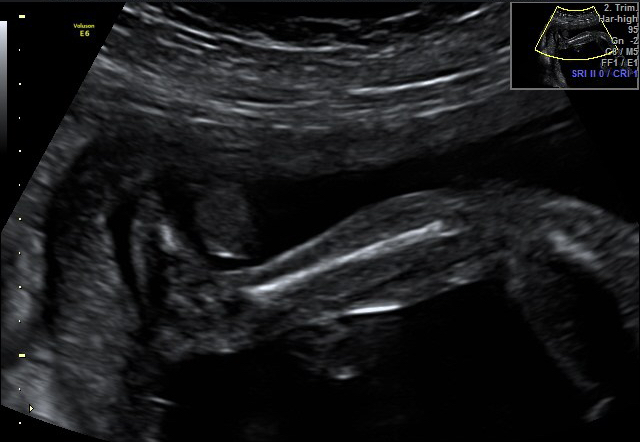

come una mamma aspetta quell’ecografia

Click dentro al pancione